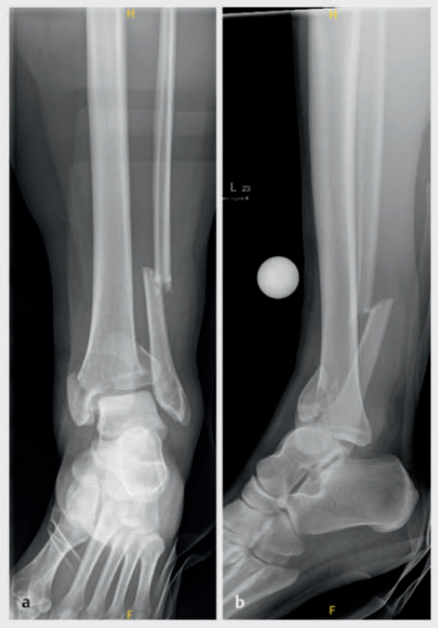

病例1在受伤后送往医院急诊,首先进行了跨踝关节外固定架。尽管患者初始存在Ⅱ度闭合性软组织损伤,但由于及时进行了复位并植入外固定架,未需实施筋膜间室切开术。在术前CT图像中,可清晰观察到3个主要骨折块及1个中央粉碎区。通过及时植入外固定架,可恢复关节位置,并有效避免软组织损伤进一步加重。

待软组织状况改善(出现 “皮肤皱纹征”)后,开始对患者进行手术治疗,首先处理腓骨(遵循 “先处理腓骨” 原则)。术中检查发现韧带联合存在不稳定情况。

术中三维CT 扫描确认骨折达到解剖复位,内植物位置良好。术后影像学检查证实骨折解剖复位,内植物位置正常。患者术后恢复过程顺利,关节功能恢复良好。